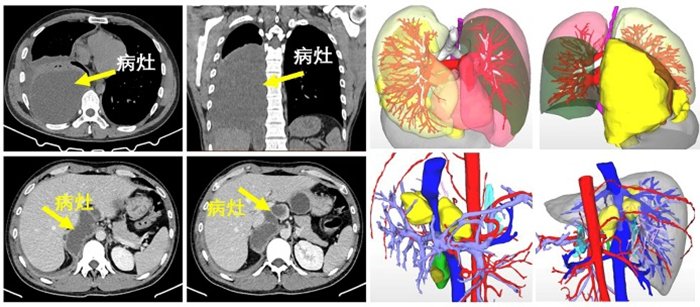

这是一名年轻男性患者,因“右上腹及肩背部疼痛5天”来到肝胆胰外科就诊。经胸部增强CT检查提示右胸腔后侧、下纵膈气管旁囊性占位性病变,右肺下叶压缩性肺不张。腹部增强CT提示肝包虫病,腹膜后多发囊性占位病变,考虑为包虫病。

肝胆胰外科杨闯主任认为患者为藏区群众,有疫区接触史,结合影像学资料,肝棘球蚴病、腹腔棘球蚴病、胸腔棘球蚴病明确,需要手术治疗。因病灶涉及多系统器官,手术较复杂,需要多学科协作完成,在医院医务部罗亦刚主任的主持下,杨闯副院长邀请郭中恒院长、麻醉科曾浩主任等科室负责人开展MDT(多学科会诊)讨论。

通过讨论一致认为,从多维度考量,胸、腹部病灶同期手术切除的方案是可行的,取得患者家属同意后,决定为患者实施胸腹腔病损切除、右肺部分切除、肝部分切除等手术。

经充分术前准备,赵科医生担任主麻,曾浩主任为麻醉指导,郭中恒主任医师主刀为患者实施右侧胸部病损切除、部分肺切除术,接着由杨闯主任医师为患者实施肝部分切除联合腹膜后包虫切除术,历经近9小时奋战,手术顺利完成。